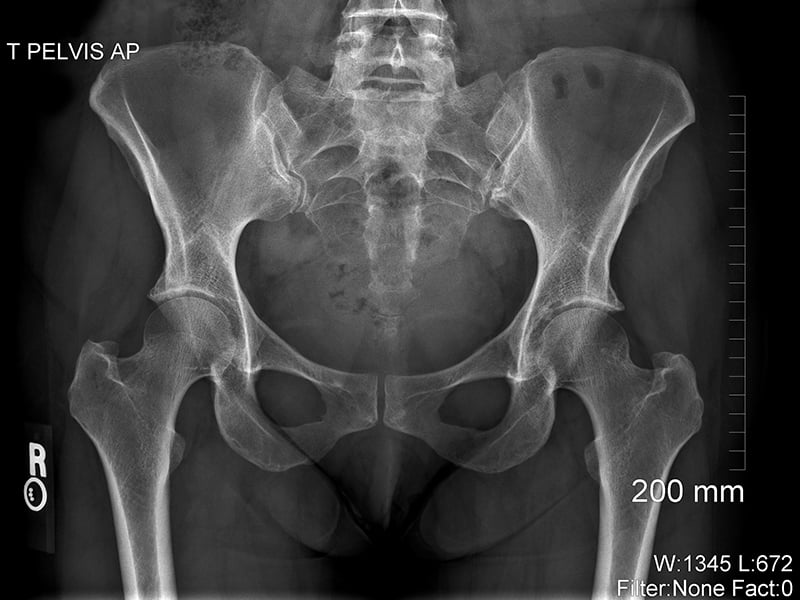

X-rays are a type of radiation. They’re an energy source similar to light, but they have a much shorter wavelength and can pass through the human body. As x-rays pass through the body, some energy particles called photons are absorbed, and some pass all the way through. The parts of the body made up of dense material, such as bone, show up as white areas on an x-ray image (the image itself is called a ​radiograph). The less dense parts, like the lungs, show up as darker areas.

X-ray of pelvic

X-ray

Image © ASRT